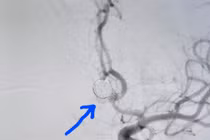

Đau đầu triền miên, tình trạng đau đầu mạnh, tần suất nhiều, chị L. 42 tuổi (Ninh Bình) đi khám bất ngờ phát hiện khối u não nằm ở vị trí sâu nhất trong não.